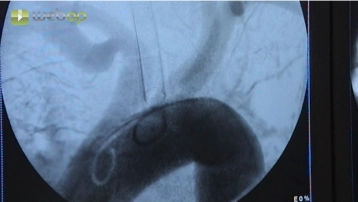

Punktion der A. femoralis rechte Leiste nach Seldinger und vorsichtiges Einführen des Führungsdrahtes. Nach Entfernung der Punktionskanüle Einführen einer 6- oder 7-F-Schleuse unter Durchleuchtungskontrolle. Entfernung des Führungsdrahtes und Kontrolle des pulsatilen Rückstroms, sodann lokale Gabe von 5000 IE Heparin-Kochsalz-Lösung. Unter Duchleuchtungskontrolle Einführen eines langen Terumo®-Drahtes in die rechte Beckenstrombahn und die Aorta.